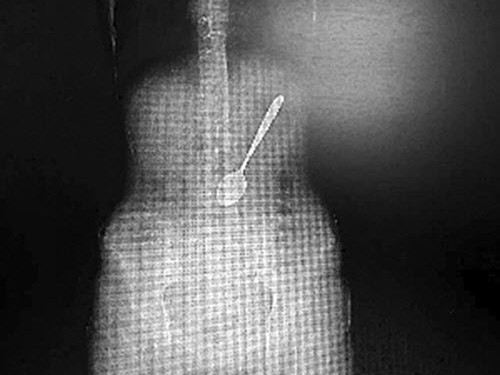

![]() |

| Đây là một chiếc muỗng làm từ thép không gỉ, cạnh tròn nên gây khó khăn trong việc lấy ra ngoài. |

Sau khi kiểm tra, tình trạng của cô gái nghiêm trọng hơn nhiều so với những gì các bác sĩ nghĩ ban đầu. Bằng cách chụp X-Quang, bác sĩ đã phát hiện ra chiếc muỗng dài hơn 15cm trong bụng cô Wang, nằm chếch một góc 30 độ.

Theo bác sĩ, chiếc muỗng có thể trượt vào ruột bất cứ lúc nào. Nếu điều đó xảy ra, chiếc muỗng có thể làm thủng dạ dày và gây tổn thương nội tạng, thậm chí có thể dẫn tới tử vong. Từ đó, các bác sĩ đã quyết định lấy chiếc muỗng ra theo đường nó đã đi vào.